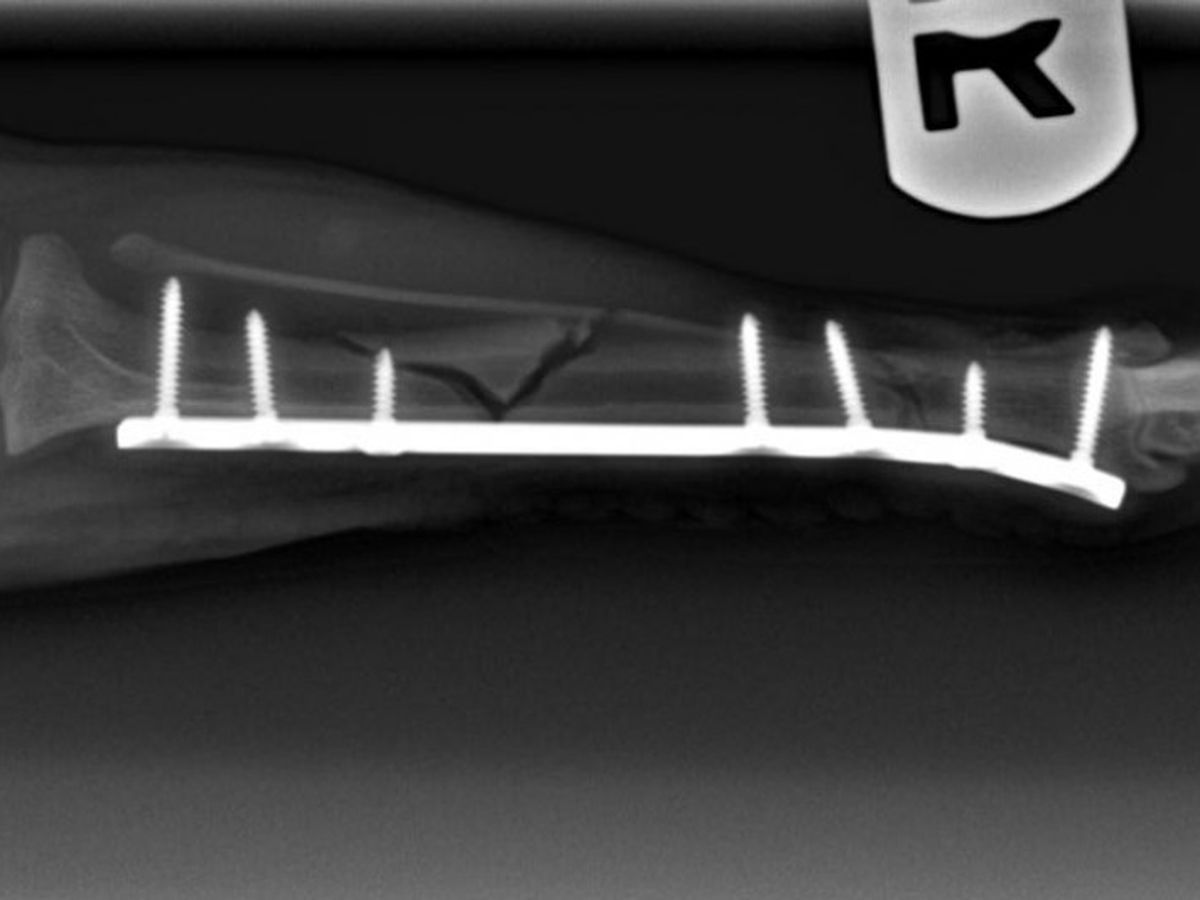

During our holiday trip up to NorCal to visit family, our beloved little chihuahua, Chiqui, that many of you know and love, was involved in an accident which resulted in her right, back leg being broken fairly severely. The break and additional fracture occured in both her tibia and fibula bones and were extensive enough to require an expensive surgery and recovery process: about $1,500 for the initial emergency care and hospitalization and $5,500 for the surgery and medication.